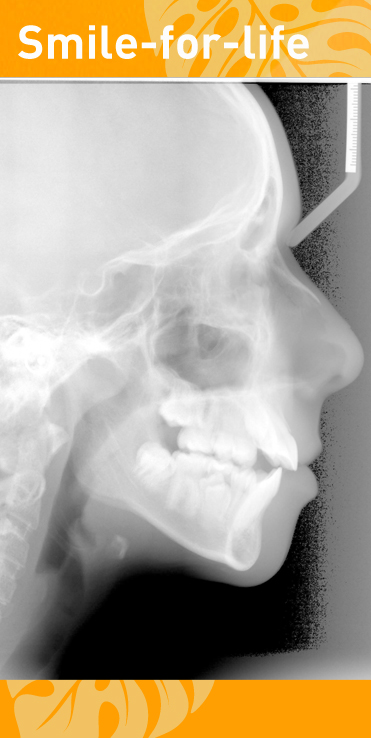

Digitales Röntgen

Digitale Röntgenaufnahmen ersetzen das analoge Röntgen und haben eine bis zu 90 Prozent reduzierte Strahlenbelastung gegenüber[...]